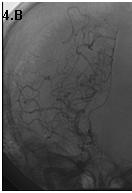

Mujer de 46 años que ingreso por cefalea súbita, hemiparesia izquierda y disartria, con tomografía axial computarizada cerebral simple que mostró hemorragia frontoparietal derecha drenada a ventrículos y arteriografía con patrón Moyamoya. Reingreso 3 meses después con deterioro del estado de consciencia y tomografía axial computarizada cerebral simple que mostró hemorragia intraparenquimatosa temporoparietal izquierda con extensión intraventricular y desviación de la línea media, se manejo en Unidad de Cuidados Intensivos con traqueostomía y gastrostomía, presentó neumonía y sepsis nosocomial, finalmente falleció en la Unidad de Cuidados Intensivos.